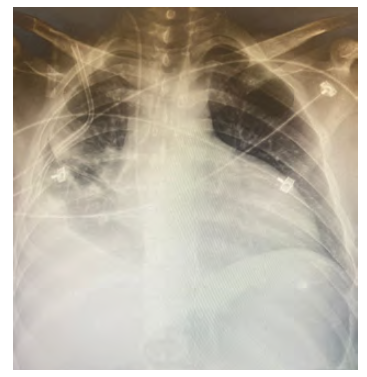

A 29-year-old male patient with chronic kidney disease secondary to renal hypoplasia with no family history had been diagnosed at age 20 years and had renal replacement therapy for 5 years by peritoneal dialysis. Anemic syndrome was treated with erythropoietin 4000 IU at twice a week. For difficult-to-control secondary arterial hypertension, the patient received nifedipine 30 mg every 12 hours, losartan 50 mg every 12 hours, and metoprolol 50 mg every 12 hours orally. In the previous 2 years, the patient had been hospitalized for generalized fatigue, weakness, progressive dyspnea, and changes in skin color. Anemia had been detected with hemoglobin level of 7.8 g/dL. Chest radiography showed right pleural effusion (Figure 1), and thoracic echocardiogram showed dilatation of the left ventricle, with preserved function left ventricular ejection fraction of 48%, enlargement of the left atrium with moderate to severe mitral regurgitation with regurgitant fraction >40%, and vena contracta width of 0.44 cm.

Figure 1. Chest Radiography With Pulmonary Congestion and Right Drainage Tube